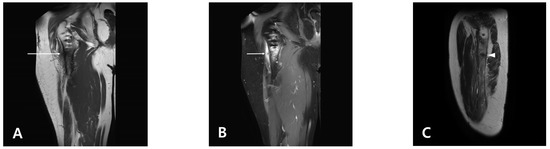

Subtrochanteric Insufficiency Fracture Occurring 5 Years after Surgery at the Steinmann Pin Insertion Site for Fracture Reduction